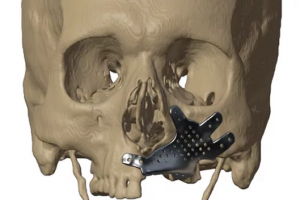

利用有限元分析优化个性化的上颌植入物设计【Simpleware应用】

概述 Jajal Medical 公司使用 Simpleware 软件将患者的扫描数据(如CT、MRI)转换为适用于可视化和规划复杂手术的 3D STL 格式和有限元(FE)模型。数字化手术规划有助于降低手术期间意外并发症的风险、缩短手术室(OR)时间、节省资金以及改善临床结果和患者满意度,因此此类工作流程变得越来越有价值。 在这个案例中,患者被确诊为毛霉菌病,导致左上颌骨大面积缺损,Jajal Medical 需要为其优化个性化的上颌植入物设计。过程中运用到 Simpleware 和 Ansys 两款软件。 亮点 使用 Simpleware ScanIP 导入和可视化 CT 扫描,分割出骨骼使用 Ansys 软件进行骨骼/医疗器械间的交互模拟3D 打印患者特定骨骼模型和个性化植入物虚拟手术规划协助最终的手术和植入 3D可视化和分割 采用适当层厚的高分辨率 CT 扫描数据可视化上颌解剖结构及邻近区域。在 Simpleware ScanIP 软件中导入 CT 数据,执行分割并重建 3D 解剖模型,帮助外科医生更好地可视化和理解手术。 图:采用Simpleware软件分割颅骨CT数据 个性化植入物的设计 鉴于患者左侧上颌骨骼明显缺失,在 Geomagic Freeform 软件中以健康的右侧作为参考设计上颌植入物。然后将健康的右侧上颌骨镜像并与现有上颌重叠。这种方法有助于在缺损处重建上颌骨,确保对称性和美观。此外,在植入物的表面添加孔可以达到减重效果。考虑到牙齿康复,同时将标准基台的印模也合并到植入物中。 图:个性化上颌植入物的设计 有限元分析 最终位置确定后,将文件加载到 Ansys 软件中处理。Jajal 采用有限元方法解决涉及复杂几何形状的医疗结构问题,虚拟模拟实时加载条件、评估植入物应力和疲劳,继而帮助优化设计。对个性化的上颌植入物与上颌骨一起分析,研究植入物的设计安全性和性能表现。在 Ansys 中进行真实加载条件下的虚拟仿真,了解植入物设计上的应力情况。结果显示植入物上的 Von Mises 应力为 93.29 […]